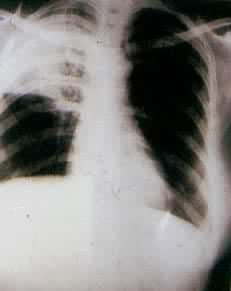

肺部疾病在诊断治疗上的新技术和新方法X线断层摄影和计算机断层扫描(CT)提供了对肺部阴影、肿块形态、性质的更明确的了解。纤维支气管镜检查,必要时还可经皮肤穿刺肺活检组织进行病理、细菌、生化的检验,大大提高了病因学的确诊率。支气管肺泡灌洗液可在镜下进行细胞计数、分类和测定液体内免疫抗体、补体与酶类,以帮助对疾病性质的了解。利用放射性核素67Ga(67镓)进行肺扫描:67Ga可以集聚在新陈代谢活跃的部位,临床上用以诊断肺癌、结节病、间质性肺泡炎等。并可用以鉴别肺梗塞与肺炎。肺动脉造影术有助于对肺梗塞的诊断。临床治疗方面:新的药物应用,如各种新型抗生素、抗结核药物、肾上腺皮质激素、平喘药物;血气分析、呼吸机的作用;建立呼吸监护室,提高了肺部感染、呼吸衰竭等疾病的诊治水平。